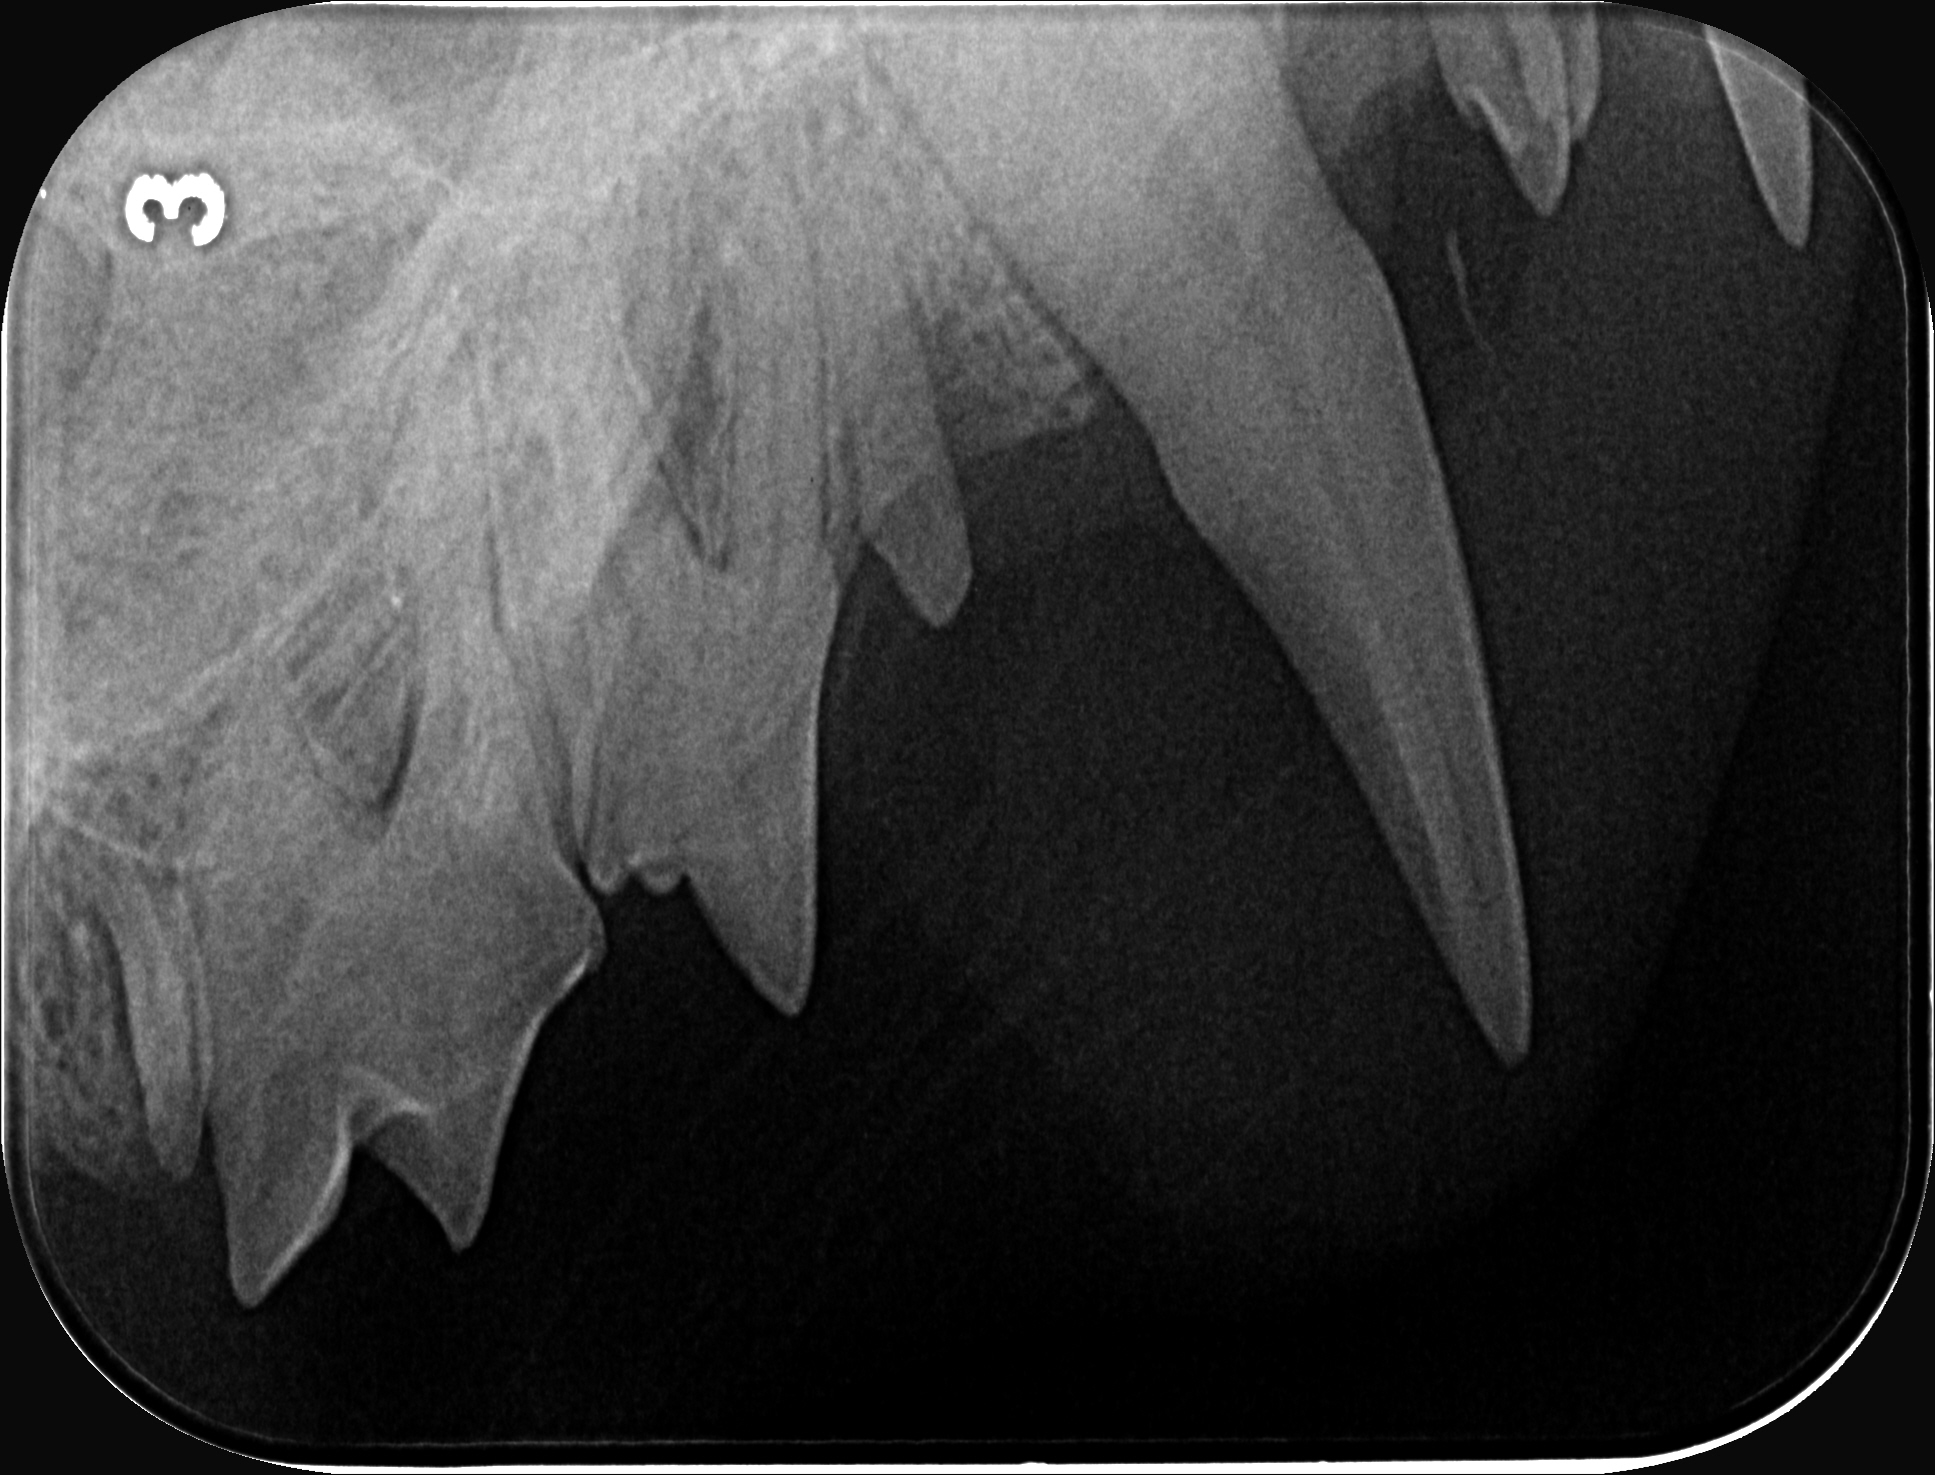

Und dann kam die Untersuchung. Und dann kam das Thema Zahnsanierung.